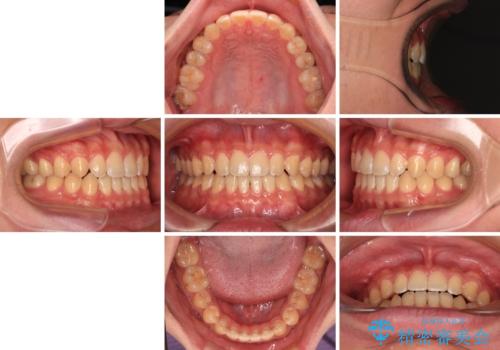

舌の突出癖がなかなか改善されず、治療期間は当初予定よりも大分長くなりました。

装置除去を予定していた日に、油断されたのか1mmほどのスペースを作ってしまったため、除去が3ヶ月延長されたことで、舌のトレーニングの重要性を理解していただきました。

装置除去後もトレーニングを継続されているようで、後戻りによるスペースは今のところ認められておりません。